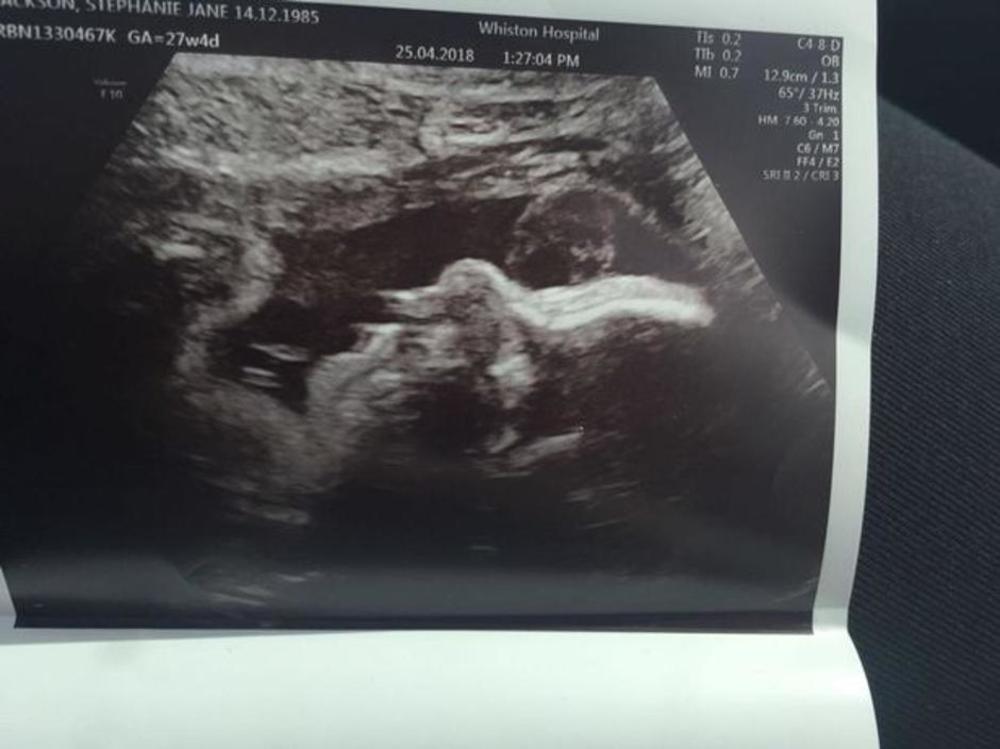

Dok mnogi roditelji na snimcima s ultrazvuka ne mogu da razaznaju ni sopstveno dete, jedna majka tvrdi kako je na fotografiji koju je dobila nakon ultrazvuka uočila lice svoje pokojne bake. Stefani Džekson (32) iz engleskog Liverpula prekjuče je posetila svog ginekologa u 18. nedelji trudnoće, a on joj je odmah napravio i ultrazvuk. No, kada je dobila fotografiju svog nerođenog deteta, iznad njega je ugledala nešto što ju je rasplakalo.

Iako je to uistinu teško uočiti, 32-godišnjakinja i njena majka tvrde kako se iznad deteta vidi lice njene pokojne bake, koja je preminula pre 14 godina, a s kojom je ova buduća majka bila jako povezana. Trudnica kaže kako se molila baki za dete jer nije bila sigurna hoće li ona i njen partner uspeti da začnu.

Naime, njen partner, Majkl Dejvis, imao je vazektomiju pre nego što su se upoznali, zbog čega je ona bila u strahu kako nikada neće imati dete. Međutim, on je prošle godine išao na takozvani "obrnuti zahvat", kojim je poništio vazektomiju, te je Stefani nakon toga uspela da začne. – Majka je prva uočila baku, no prepoznala sam je i ja kao i svi naši prijatelji i rodbina. Užasno sam emotivna zbog toga i od juče plačem – kaže buduća majka koja je toliko uverena da se na snimku nalazi njena baka, da je odmah svoju priču ispričala lokalnim novinama, nakon čega je postala pravi viralni hit.